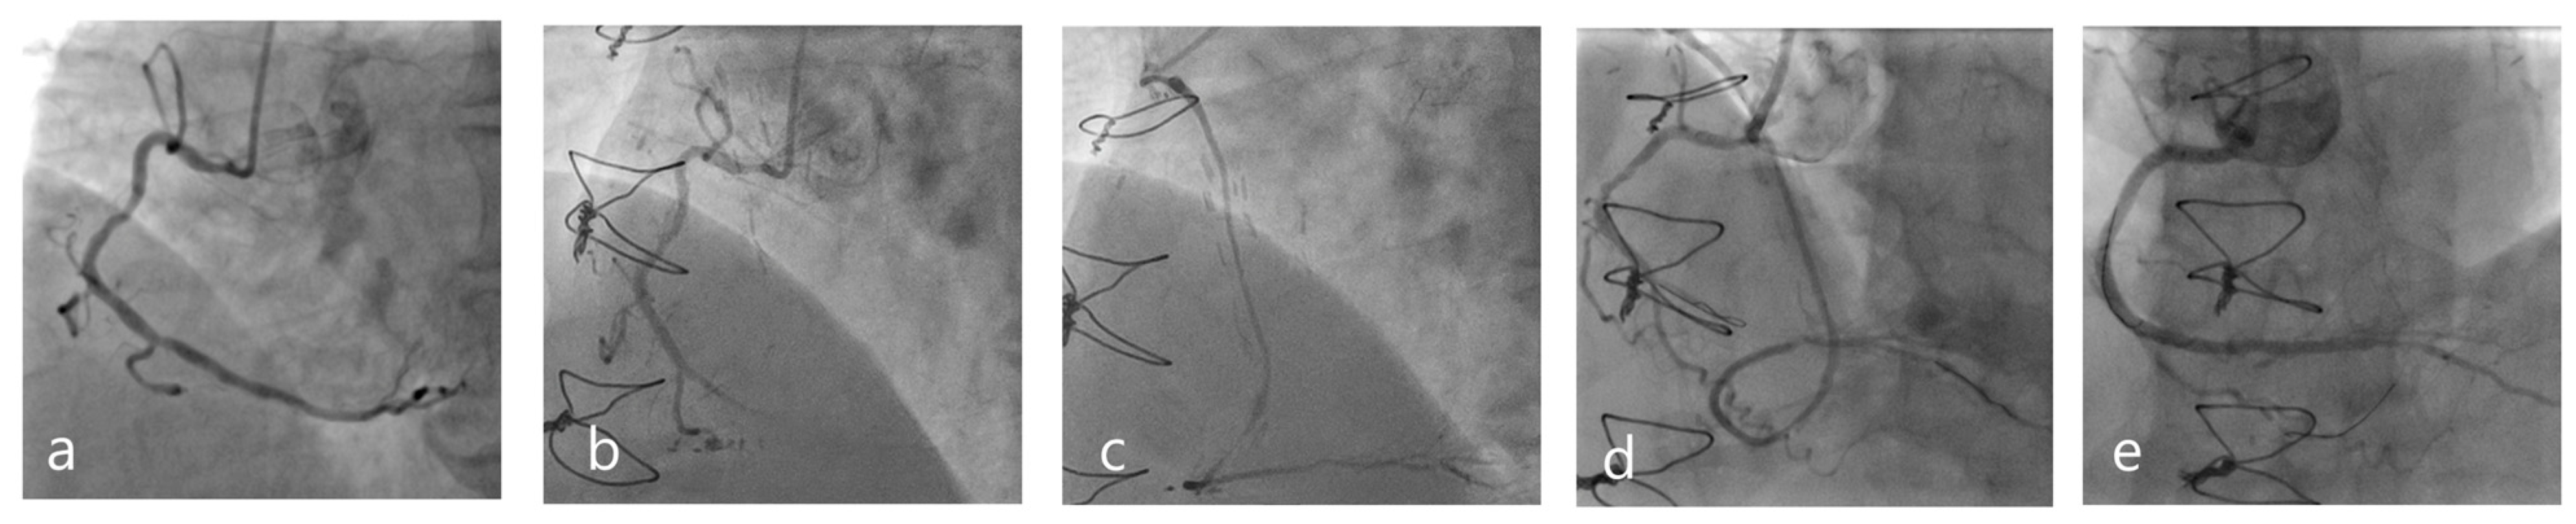

- Al-Lamee, R.; Ielasi, A.; Latib, A.; Godino, C.; Ferraro, M.; Arioli, F.; Mussardo, M.; Piraino, D.; Figini, F.; Carlino, M.; et al. Clinical and Angiographic Outcomes after Percutaneous Recanalization of Chronic Total Saphenous Vein Graft Occlusion Using Modern Techniques. Am. J. Cardiol. 2010, 106, 1721–1727. [Google Scholar] [CrossRef]